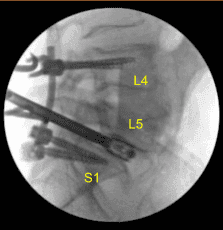

The patient was draped sterilely. Intraoperative CT scan was obtained and the data was transferred to the neuronavigation computer. Accuracy was verified and neuronavigation techniques were used to place pedicle screws in the L4, L5, and S1 pedicles bilaterally.

X-rays were repeated to confirm correct positioning and size. Neuromonitoring signals were stable. Next with the left L5 pedicle completely isolated and exposed, we placed left L5 pedicle screw decorticating with electric high-speed drill cannulating with the curved freehand Lenke pedicle finder palpating for breaches using 5.0 mm tap and placing 45 mm x 6.0 diameter titanium pedicle screw without difficulty.

We then similarly placed a right L5 pedicle screw as well using similar technique. We draped the patient sterilely and obtained an intraoperative CT scan which showed correct positioning of all the pedicle screws and interbody spacer.

Precut and precontoured titanium rods were selected and placed across the tulips and secured with locking caps, which were all final tightened with torquing and anti-torque devices at L4, L5 and S1. Morselized demineralized bone matrix autograft collected from the decompression as well as bone morphogenic protein allograft were packed into the lateral gutters from L4 to S1 to the posterolateral arthrodesis.

We took final AP and lateral x-rays, which showed correct positioning of all the hardware. The closure will be dictated separately. At the end of the case, the patient was turned supine on the cart, and transported to the recovery room in stable condition.